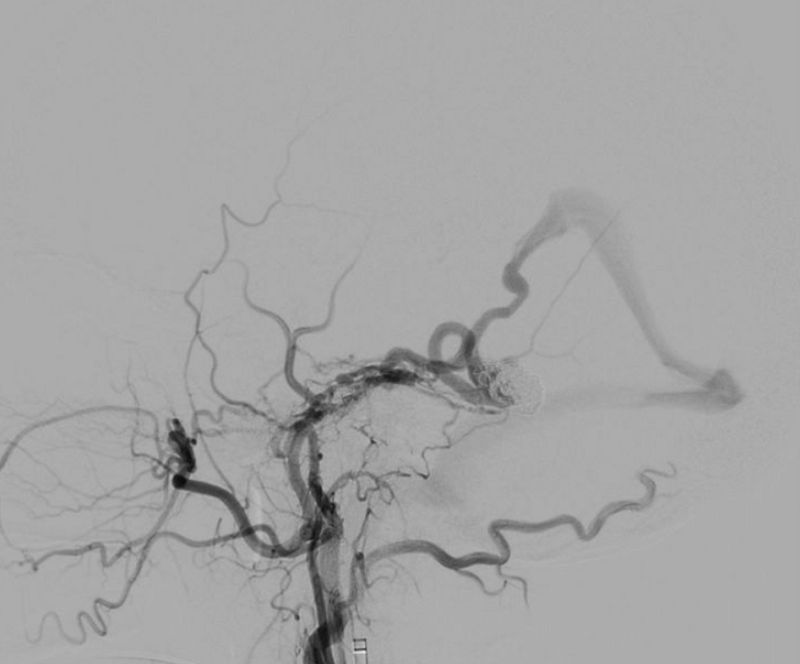

Instead of traditional open skull surgery, the doctors decided to apply endovascular intervention. This is an advanced, minimally invasive, highly effective treatment method but requires the doctor’s skill. The patient was immediately taken to the Cathlab. Dr. Huynh Huu Danh directly performed the endovascular intervention with the support of a DSA digital subtraction angiography machine.

Dr. Danh said that because the aneurysm was located in a difficult-to-reach location, the doctor had to insert the catheter through the vein instead of the artery. “If intervention through the artery is like driving on a flat asphalt road, intervention through the vein is like going through rugged, bumpy, winding terrain, with a higher risk of complications,” Dr. Danh compared.

From a small incision in the thigh, Dr. Danh skillfully inserted the catheter and a microscopic guide wire from the vein, moving to the aneurysm area in the brain, placing a total of 12 coils (spiral-shaped metal coils) inside the aneurysm to “patch” the damaged area, blocking the blood flow through the ruptured aneurysm.

Treatment of dural arteriovenous fistula or cerebral aneurysm by endovascular intervention has the advantage of being minimally invasive and having a high success rate. However, this method needs to be performed in a modern Cathlab, by doctors specializing in endovascular intervention and neurointervention. FV Hospital has a modern Cathlab, a DSA angiography machine that produces clear vascular images, helping to perform more precise operations and shortening intervention time. Dr. Huynh Huu Danh is one of the experienced endovascular intervention specialists, who can perform the procedure on both children and adults.